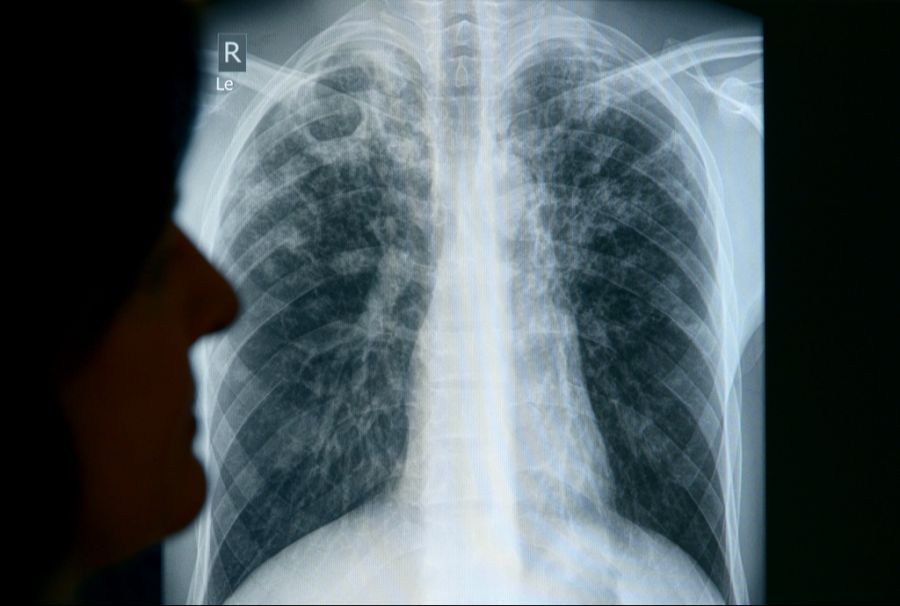

Tuberkulose-Fälle nehmen in der Schweiz zu. Das liegt wahrscheinlich daran, dass vermehrt Menschen aus Regionen mit einer hohen Häufigkeit von Tuberkulose in die Schweiz einwandern. Das teilte das Bundesamt für Gesundheit (BAG) der Nachrichtenagentur Keystone-SDA mit.

Die Tuberkulose wird durch bestimmte Arten von Mykobakterien verursacht, am häufigsten durch das Mycobacterium tuberculosis. Die Übertragung erfolgt, indem eine an Lungentuberkulose erkrankte Person bakterienhaltige Tröpfchen aushustet. Diese Tröpfchen schweben dann in der Raumluft und werden von anderen eingeatmet.

Für eine Ansteckung ist meist ein Aufenthalt im gleichen Raum über Stunden erforderlich.